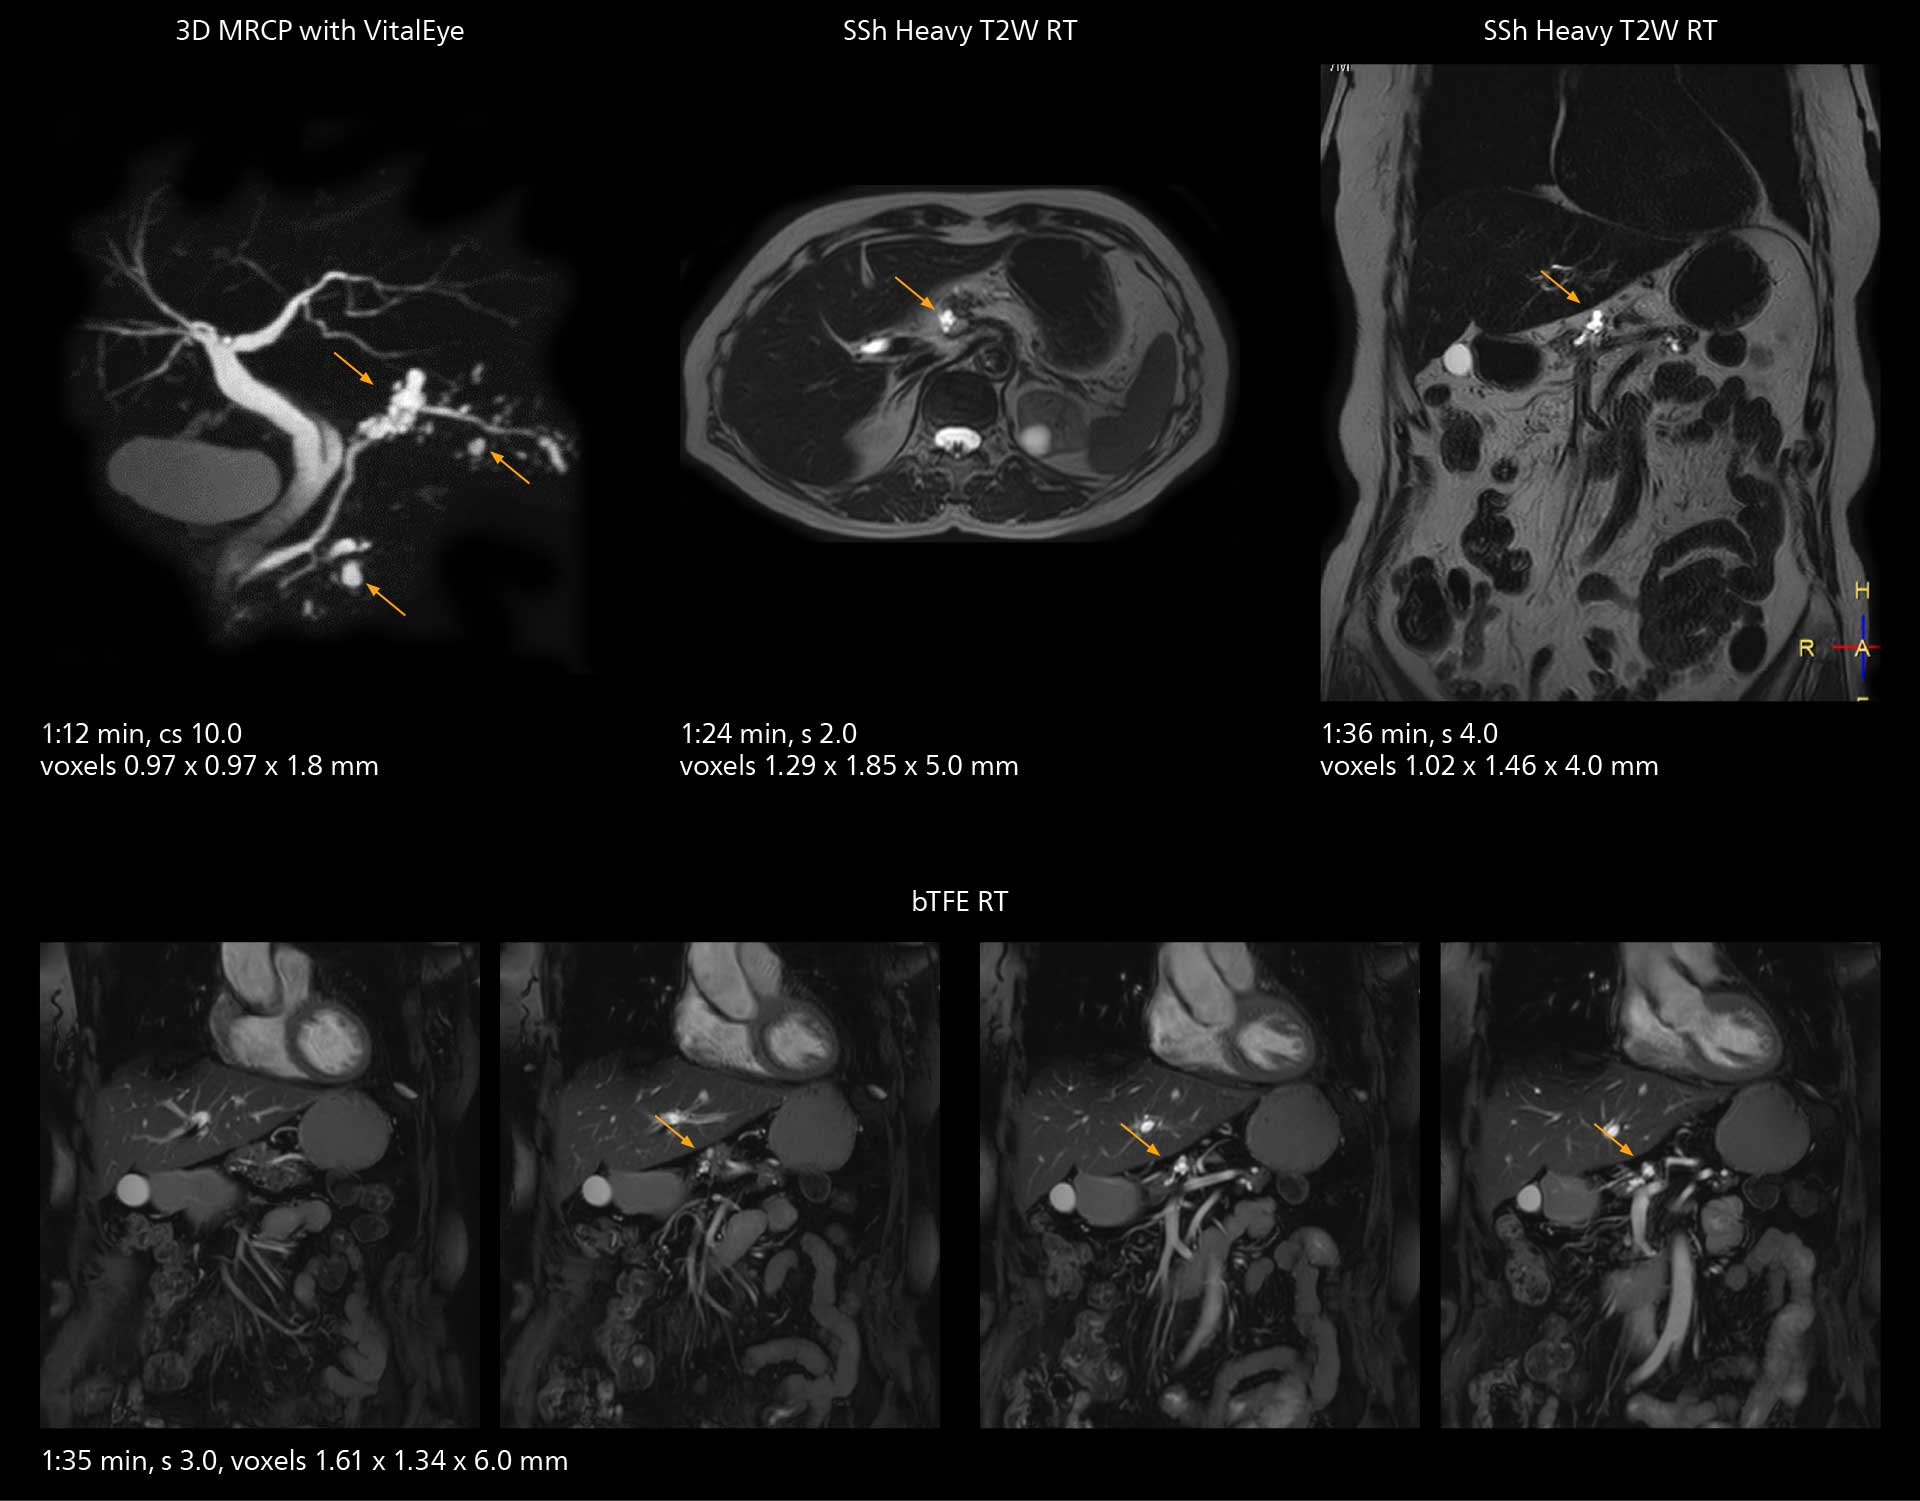

SmartPath to Elition X comes with Smart Workflow technologies that support technologists and can save them time. VitalEye for touchless patient sensing is one example.

“The implementation of VitalEye respiratory synchronization has had a significant impact,” says MR technologist Yoshihiro Otsu, Chief of the Radiological Department. “It not only improves workflow, but it also has increased the quality of examinations. Particularly for the large number of MRCP examinations performed in this hospital, VitalEye has increased the possibility to obtain sharp images with less blurring. Clinicians here really appreciate this improvement in MRCP image quality.”

MRCP

With SmartPath to Elition X, the MRCP examinations at Sannodai Hospital benefit from VitalEye: respiratory synchronization is possible without respiratory belt positioning and image quality is excellent.